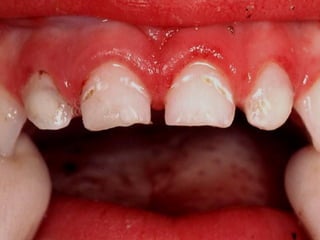

Menor de 3 años con

cualquier evidencia

de caries en

superficie lisa

3, 4, 5 años con

superficie lisa de

incisivo central

Las primeras lesiones no son cavitadas

a medida que pasan los años

aparecen más lesiones cavitadas